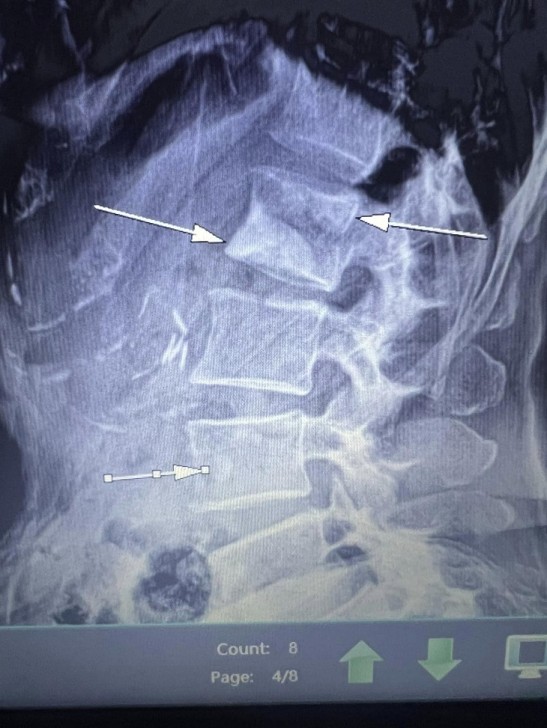

AFN.az xəbər verir ki, tanınmış həkim Aydın Əliyev bu sahədə vəziyyətin getdikcə ağırlaşdığını bildirib. O, xəstələrdən birinin müayinə nəticələrini paylaşaraq bunları yazıb: “Onkoloji xəstəliklərin müayinə və müalicəsinin hələ də icbari tibbi sığorta tərəfindən qarşılanmamasının daha bir qurbanı. Sağ qamış sümüyündəki törəmənin maddi imkansızlıq səbəbindən vaxtında və sistemli müalicə və ya əməliyyat edilməməsi səbəbindən fəqərələrə, qabırğalara, kürək, çanaq sümüklərinə, ağciyərə çoxsaylı metastazları. Demək olar ki, adam həyatını itirib”.